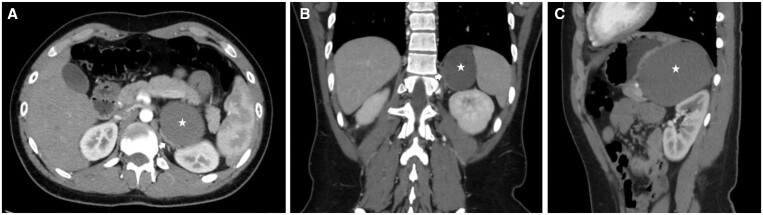

Bronchogenic cysts are rare lesions that form during early embryogenesis and are commonly located in the mediastinum. Retroperitoneal bronchogenic cysts (RBs) are exceptionally rare, with only a handful of cases reported in the modern literature. Here, we report an RB found incidentally on imaging in a patient with suspected nephrolithiasis. We also review the unique imaging and histopathological findings of this entity and discuss why prophylactic surgery is considered the treatment of choice.